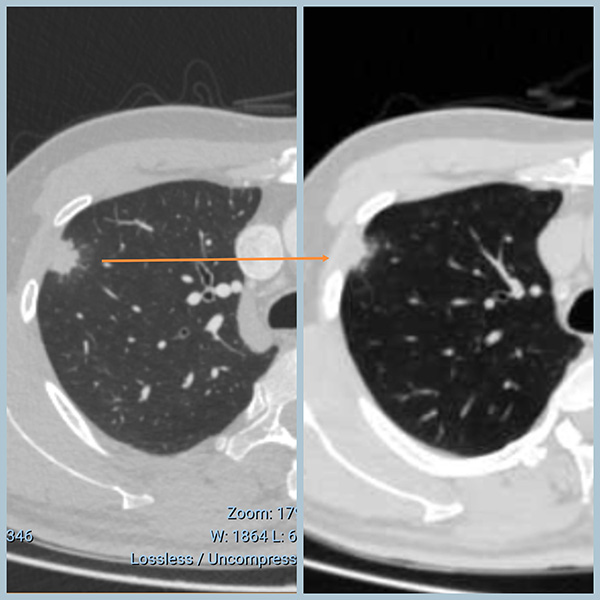

一个月后复查:病灶明显吸收、变小!不是恶性!

患者问我的时候,先拿出来的是最近的CT(消炎后的)

最近的CT因病变已经缩小、吸收,恶性特征不明显了

两次CT对比,变化(缩小吸收)一目了然!

这个时候,即使是医学生也知道不可能是恶性的了。